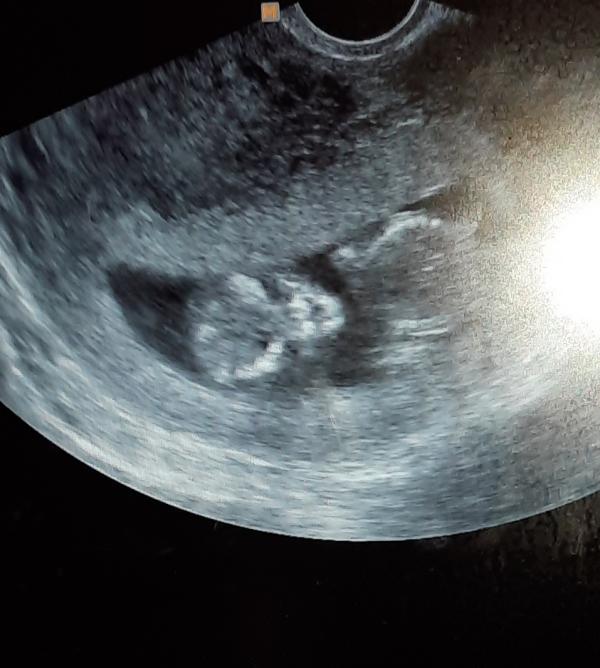

Наш малышок🥰🥰🥰Первый скрининг, по УЗИ всё хорошо, осталось дождаться анализа крови